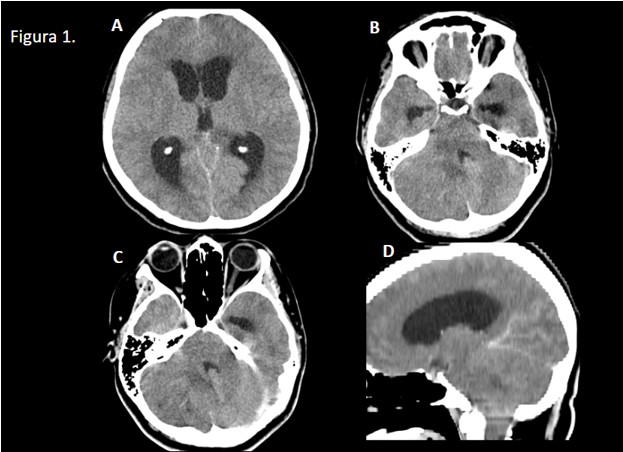

Figura 1: TC secuencial de cráneo sin CIV (A y B) y con CIV (C y D).

Lesión focal sólida en hemisferio cerebeloso derecho, isodensa al parénquima, que muestra pequeños focos hiperdensos en su interior sugestivos de microcalcifcaciones, con efecto masa muy significativo sobre el parénquima adyacente. La lesión comprime el IV ventrículo y condiciona hidrocefalia obstructiva tetraventricular, obliteración de surcos cerebrales y herniación de las amígdalas cerebelosas a través del agujero magno.

Tras la administración de contraste iv, no se objetivan realces significativos.